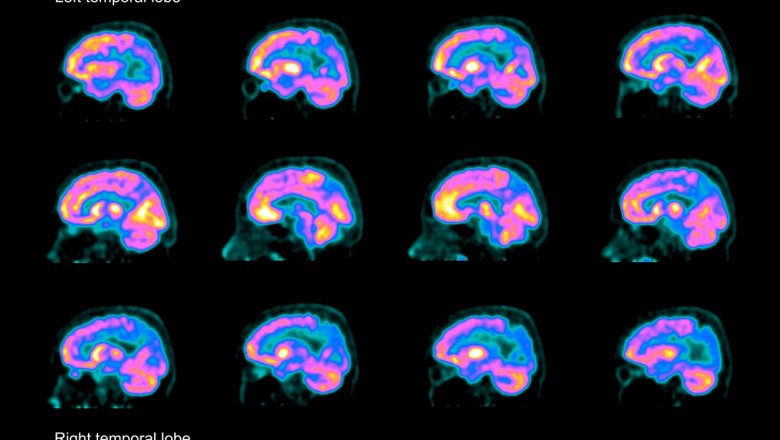

Pe site-ul său, compania descrie medicamentul simufilam ca pe "o abordare cu totul nouă în tratarea maladiei Alzheimer", cea mai răspândită formă de demenţă ce afectează aproximativ 6 milioane de americani. Medicamentul care se ia pe cale orală reface forma normală şi funcţiile unei proteine cheie din creier, conform companiei.